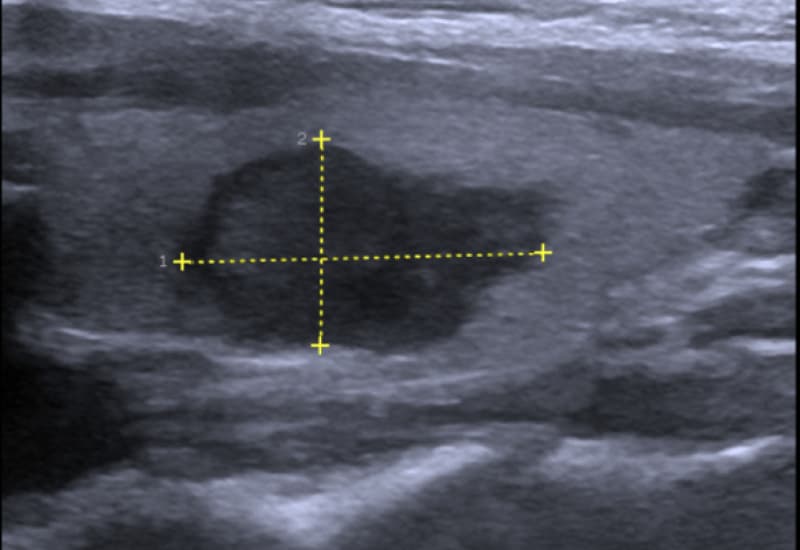

Với thắc mắc “siêu âm có phát hiện được u tuyến giáp không?” thì câu trả lời là có. Qua hình ảnh siêu âm, bác sĩ có thể nhận diện các khối u, nhân giáp hoặc nang giáp, đồng thời đánh giá đặc điểm của chúng như kích thước, vị trí, cấu trúc rắn hay nang, bờ đều hay không đều, mức độ xâm lấn mô xung quanh và hạch bạch huyết vùng cổ. Những yếu tố này giúp định hướng nguy cơ lành tính hay ác tính của khối u.

Siêu âm tuyến giáp không chẩn đoán xác định được ung thư tuyến giáp nhưng là xét nghiệm đầu tay để đánh giá ung thư. Các phương pháp chẩn đoán hình ảnh khác như chụp CT, Chụp PET/CT và MRI chỉ được sử dụng khi siêu âm khó đánh giá. Các dấu hiệu nghi ngờ ung thư tuyến giáp trên siêu âm bao gồm:

- Khối giảm âm tối hơn so với mô tuyến giáp bình thường.

- Bờ khối u không đều, có hình răng cưa.

- Hình ảnh taller-than-wide với trục dài vuông góc với bề mặt da.

- Hình ảnh các chấm trắng nhỏ li ti (vi vôi hóa).

- Tăng lưu lượng tuần hoàn tại vùng u trên hình ảnh siêu âm Doppler.

- Hạch cổ to bất thường, giảm âm và mất cấu trúc rốn trung tâm.